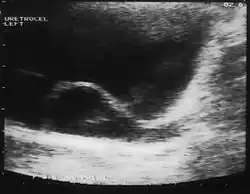

A ureterocele is a congenital abnormality found in the ureter. In this condition the distal ureter balloons at its opening into the bladder, forming a sac-like pouch. It is most often associated with a duplicated collection system, where two ureters drain their respective kidney instead of one. Simple ureterocele, where the condition involves only a single ureter, represents only twenty percent of cases.

Since the advent of the ultrasound, most ureteroceles are diagnosed prenatally. The pediatric and adult conditions are often found incidentally, i.e., through diagnostic imaging performed for unrelated reasons.

IVU-shows Adder head appearance or Cobra head appearance. Cystoscopy-shows translucent cyst which is thin walled surrounding ureteric orifice